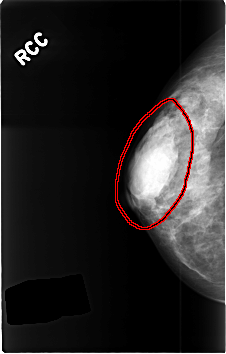

FILE: C_0430_1.RIGHT_CC.OVERLAY

TOTAL_ABNORMALITIES 1

ABNORMALITY 1

LESION_TYPE MASS SHAPE OVAL MARGINS MICROLOBULATED

ASSESSMENT 3

SUBTLETY 5

PATHOLOGY BENIGN_WITHOUT_CALLBACK

TOTAL_OUTLINES 1

BOUNDARY